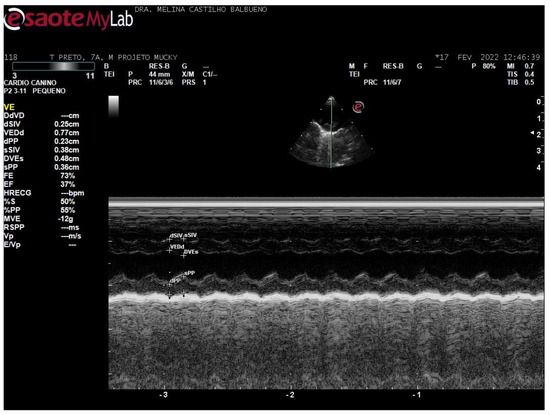

- Balbueno, M.C.S.; Martins, J.A.; Malaga, S.K.; Forato, J.; Coelho, C.P. Dilated cardiomyopathy phenotype in Callithrix penicillata (E. Geoffroy, 1812): Case report. J. Med. Primatol. 2024, 53, e12678. [Google Scholar]

de Souza Balbueno, M.C.; Martins, J.A.; Malaga, S.K.; Vanstreels, R.E.T.; de Paula Coelho, C. Echocardiographic Parameters of Callithrix spp. Under Human Care. Animals 2025, 15, 1875. https://doi.org/10.3390/ani15131875